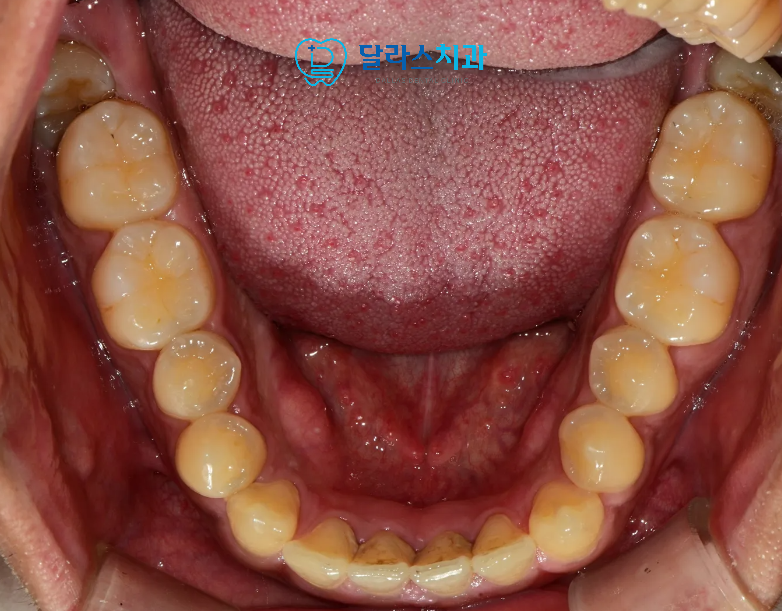

또한 입안쪽으로는 잇몸 경계부분을 따라서 착색이 진행되어 있었습니다.

아래의 경우에는 치석까지 잇몸쪽으로 깊이 쌓여있어서

치석제거까지 함께 진행되어야 하는 상황이었습니다.

이에 따라 AirFlow와 PS 팁을 병행한 스케일링과 착색제거를 진행하였으며

아래는 치석까지 깔끔하게 제거되어

치주건강까지 신경쓴 관리가 이루어졌습니다.